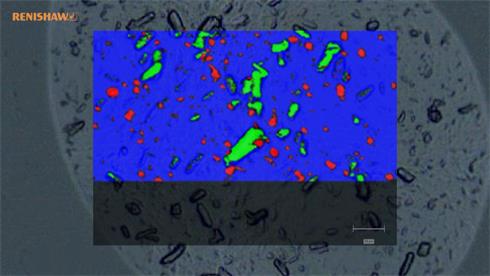

- Generate images of the formulations used in tablets, inhalers and nasal sprays at sub-micrometre spatial resolution

Rapidly generate images of your formulations with StreamLine™. This uses line focus illumination, allowing you to use higher laser powers without risk of sample damage, thereby reducing experiment times.

Generate images of formulations

Ensure your chemical images are representative; use Renishaw's StreamLine. You can change resolution to suit your domain size and, because Renishaw's WiRE software can cope with massive data files, you can analyse over the entire sample surface. Powerful Renishaw features, such as Slalom (to ensure the whole surface is sampled) and HD imaging (to get crisp clear images), provide all the options you need, whatever your formulation.